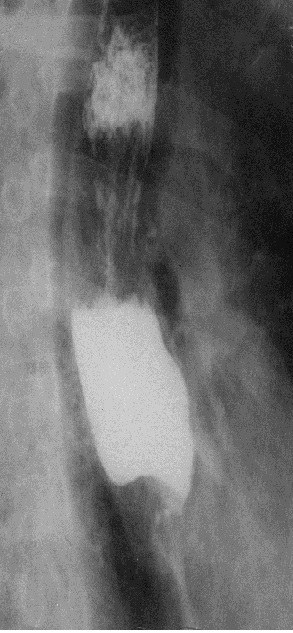

Рис. 15. Рентгенограмма пищевода в правой косой проекции. Определяется выраженное сужение средней и нижней трети его грудного отдела после перенесенного химического ожога.